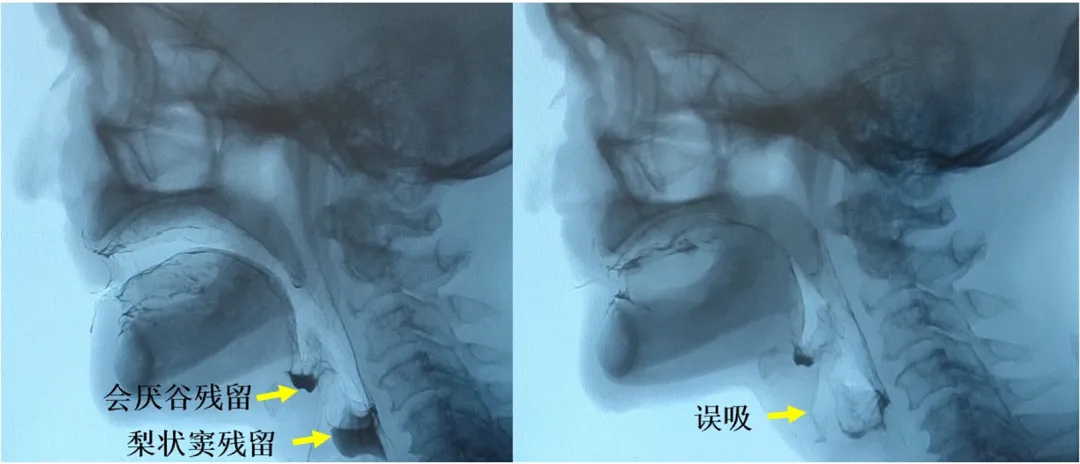

咽缩肌的病理组织改变的减轻最终在功能效应层面表现为咽缩肌功能的显著改善。造影检查显示,对比标准放疗组,内侧组咽后区豁免放疗组中出现会厌谷残留(74% vs. 100%;P<0.001)、梨状窦残留(48% vs. 73%;P=0.01)、咽后壁残留(11% vs. 27%;P=0.01)、咽通过时间>1.0秒(2% vs. 11%;P=0.03)及误吸(12% vs. 29%;P=0.03)等咽期受损表现的频率均更低(图4)。

图4:造影检查所示会厌谷残留、梨状窦残留及误吸